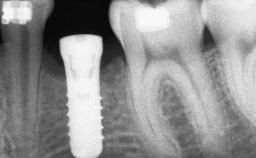

# of Implants 14

Bone Augmentation Horizontal|Sinus Floor Elevation|Staged|Vertical

Augmentation Materials Autogenous chips|Autogenous block(s)|Xenogenous|Membrane

Bone Volume Deficient vertically or deficient vertically AND horizontally